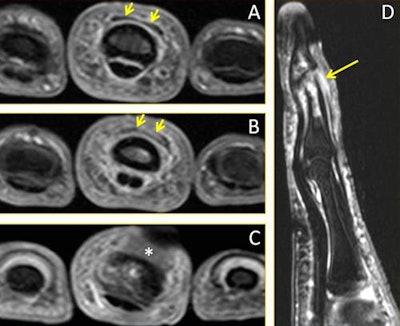

A 28-year-old male volleyball player with a finger injury. Consecutive axial fat-suppressed T2-weighted MR images of the third finger: (A) Proximally, there is normal appearance of the distal extensor tendon (short arrows); (B) Distally to A, the distal extensor tendon is thickened with increased signal intensity (arrows); (C) More distally to B, the distal extensor tendon is no longer depicted (*), consistent with a complete distal rupture. (D) Sagittal fat-suppressed T2-weighted MR image of the third finger depicts the complete rupture of the distal extensor tendon (arrow). The associated impaction fracture and bony contusions about the distal interphalangeal joint also are seen. Image courtesy of Dr. Daichi Hayashi, PhD.

A 28-year-old male volleyball player with a finger injury. Consecutive axial fat-suppressed T2-weighted MR images of the third finger: (A) Proximally, there is normal appearance of the distal extensor tendon (short arrows); (B) Distally to A, the distal extensor tendon is thickened with increased signal intensity (arrows); (C) More distally to B, the distal extensor tendon is no longer depicted (*), consistent with a complete distal rupture. (D) Sagittal fat-suppressed T2-weighted MR image of the third finger depicts the complete rupture of the distal extensor tendon (arrow). The associated impaction fracture and bony contusions about the distal interphalangeal joint also are seen. Image courtesy of Dr. Daichi Hayashi, PhD.Recent studies show the incidence of volleyball-related injuries is between 1.7 and 3.0 injuries per 1,000 hours of play, and many injuries occur due to repetitive jumping and hitting the ball overhead, he pointed out. Most injuries occur among players in front-line positions, which is where jumping and landing occur most often. Most injuries involve the lower extremities, and match injuries are more frequent than training injuries.